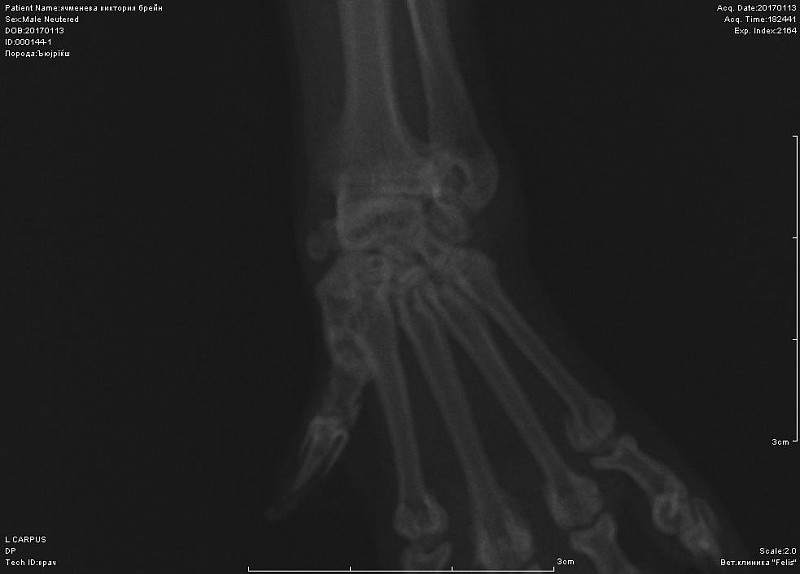

Добрый день! не вижу перелома на этом снимке. Нужна еще прямая проекция. Боль именно в запястном суставе?

К сожалению не знаем, где болит-реакции на пальпацию и энергичные движения в суставах не выявили. Именно на этом снимке врач мне указал на компрессию кости-как он сказал кость посередине должна быть квадратная, а она стала треугольной... Я сама нашла атлас посмотрела, что это нормальный вид лучевой кости.

Вот снимок, посмотрите, пожалуйста.

По-прежнему не вижу перелома, но последнее изображение увеличить не могу.

Спасибо за ответ, вот увеличила все.

вот в запястном суставе не вижу изменений.А вот локтевом есть признаки артроза. Но все же это не прямая и даже не боковая проекция локтя.